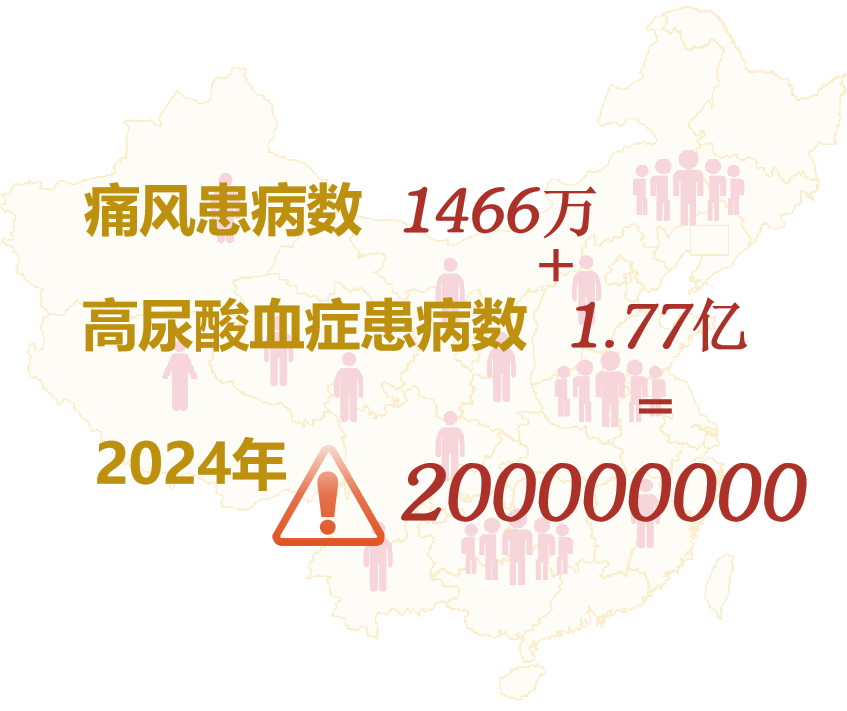

近年来,我国高尿酸血症呈明显上升和年轻化趋势,数据显示,2020年中国高尿酸血症患病人数约为 1.77 亿,痛风患病人数约为 1466 万,预计到2024年总人数将持续增长到 2 亿[1]。